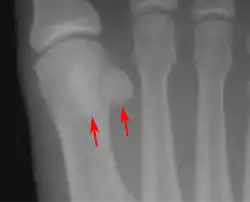

- Lateral view.[11]

- Bipartite medial sesamoid bone under the first metatarsophalangeal joint of the great toe of the left foot of an adult woman.